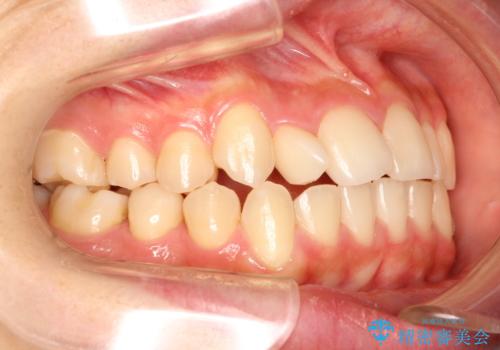

右上の側切歯(前から2番目の歯)が90度程度ねじれている状態でしたが、1月に1回のワイヤー交換できれいに並ぶことができ満足いただけました。

捻れた歯の治療に関しては、ワイヤー矯正の方が仕上がりがきれいに治りやすいです。